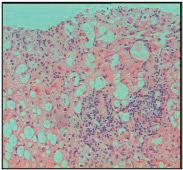

Ο βασικός σκοπός ενός εμβολίου είναι η πρόκληση μιας μακράς διάρκειας και εξει δικευμένης για το αντιγόνο προστατευτι κής ανοσολογικής μνήμης. Η λεπτομερής κατανόηση του ανοσοποιητικού συστή ματος, της βιολογίας των παθογόνων μικροοοργανισμών και των βιολογικών αλληλεπιδράσεων μεταξύ ξενιστή και παθογόνου είναι πολύ σημαντική για την ανάπτυξη των εμβολίων. Ακολουθεί μία επιγραμματική περιγραφή των βασικών σταδίων της ανοσολογικής απόκρισης κατόπιν της χορήγησης ενός εμβολίου. Αρχικά, τα συστατικά του εμβολίου (πχ. το αντιγόνο και/ή το ανοσοενισχυτικό) αναγνωρίζονται και φαγοκυτταρώνονται από κύτταρα του έμφυτου ανοσοποιητι κού συστήματος ή από αντιγονοπαρουσι αστικά κύτταρα, όπως είναι τα δενδριτικά κύτταρα και τα μακροφάγα (εικόνα 2). Οι διαδικασίες της αναγνώρισης, της φαγο κυττάρωσης και της ενδοκυτταρικής επε ξεργασίας των αντιγόνων επάγουν την ωρίμανση (κατά την οποία αυξάνεται η έκφραση μοριακών παραγόντων όπως είναι ο CD80, ο CD40 και το σύμπλεγμα μείζονος ιστοσυμβατότητας [MHC – Major Histocompatibility Complex]) και μετανά στευση των αντιγονοπαρουσιαστικών κυττάρων από τους ιστούς που βρίσκο νται στα

είναι επίσης ικανά να αναγνωρίζουν και να ανταποκρίνονται στα αντιγόνα πριν από τη συμμετοχή των Εικόνα 1 Κ ο ι ν ά σ υ σ τ α τ ι κ ά τ ω ν ε μ β ο λ ί ω ν Ε ν ε ρ γ ά σ υσ τα τι κ ά Ιικά ή βακτηριακά αντιγόνα που επάγουν άμεσα την απόκριση του ανοσοποιητικού συστήματος αλλά δεν προκαλούν νόσηση Σ τ α θ ε ρ ο π ο ι η τ έ ς Διατηρούν το εμβόλιο σταθερό μετά την παρασκευή του και διατηρούν την αποτελεσματικότητα του κατά τη διάρκεια της αποθήκευσης Σ υν τ η ρ η τ ι κ ά Εμποδίζουν την ανάπτυξη βακτηρίων και μυκητών (μόνο σε πολυδοσικά φιαλίδια των αντιγριπικών εμβολίων) Α ν ο σ ο ε ν ι σ χ υτ ι κ ά Βοηθούν στην ενίσχυση της απόκρισης του ανοσοποιητικού συστήματος στο εμβόλιο Α ν τ ι β ι ο τ ι κ ά Εμποδίζουν την επιμόλυνση του εμβολίου από βακτήρια κατά τη διάρκεια της παρασκευής του Ί χ ν η ά λ λ ω ν σ υ σ τ α τ ι κ ώ ν Εναπομείναντα μη δραστικά συσταστικά όπως η φορμαλδεΰδη και τα συστατικά κυτταροκαλλιεργειών πχ ζελατίνη πχ νεομυκίνη πχ Alum, LNPs πχ Thimerosal πχ φορμαλδεΰδη Εικόνα 1. Σχηματική αναπαράσταση των κοινών συστατικών των εμβολίων.